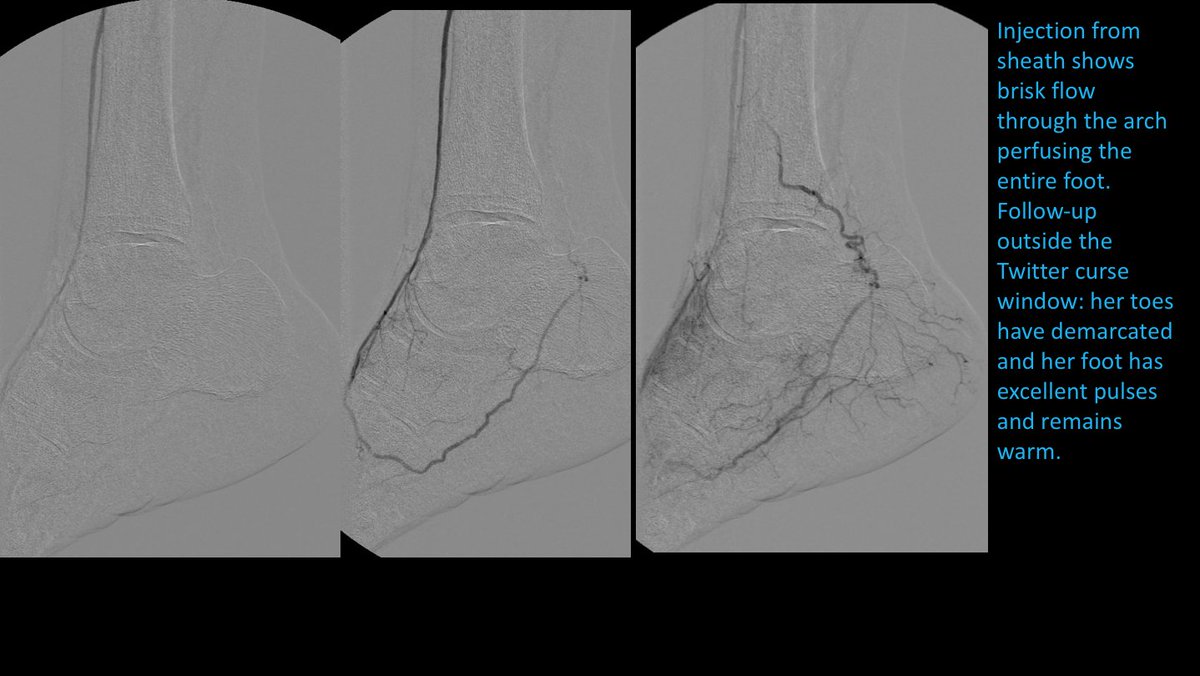

82 yo F with R5 ulcers of 3rd & 4th toes. #IRad can help with infrapopliteal and pedal revascularization to #StopTheChop. #mylegmylife #CLIFighters @SIRspecialists @SIRRFS @CLI_Global @AMPSymposium @pj_rochon

AlexCVIR's tweet image. 82 yo F with R5 ulcers of 3rd & 4th toes. #IRad can help with infrapopliteal and pedal revascularization to #StopTheChop. #mylegmylife #CLIFighters @SIRspecialists @SIRRFS @CLI_Global @AMPSymposium @pj_rochon